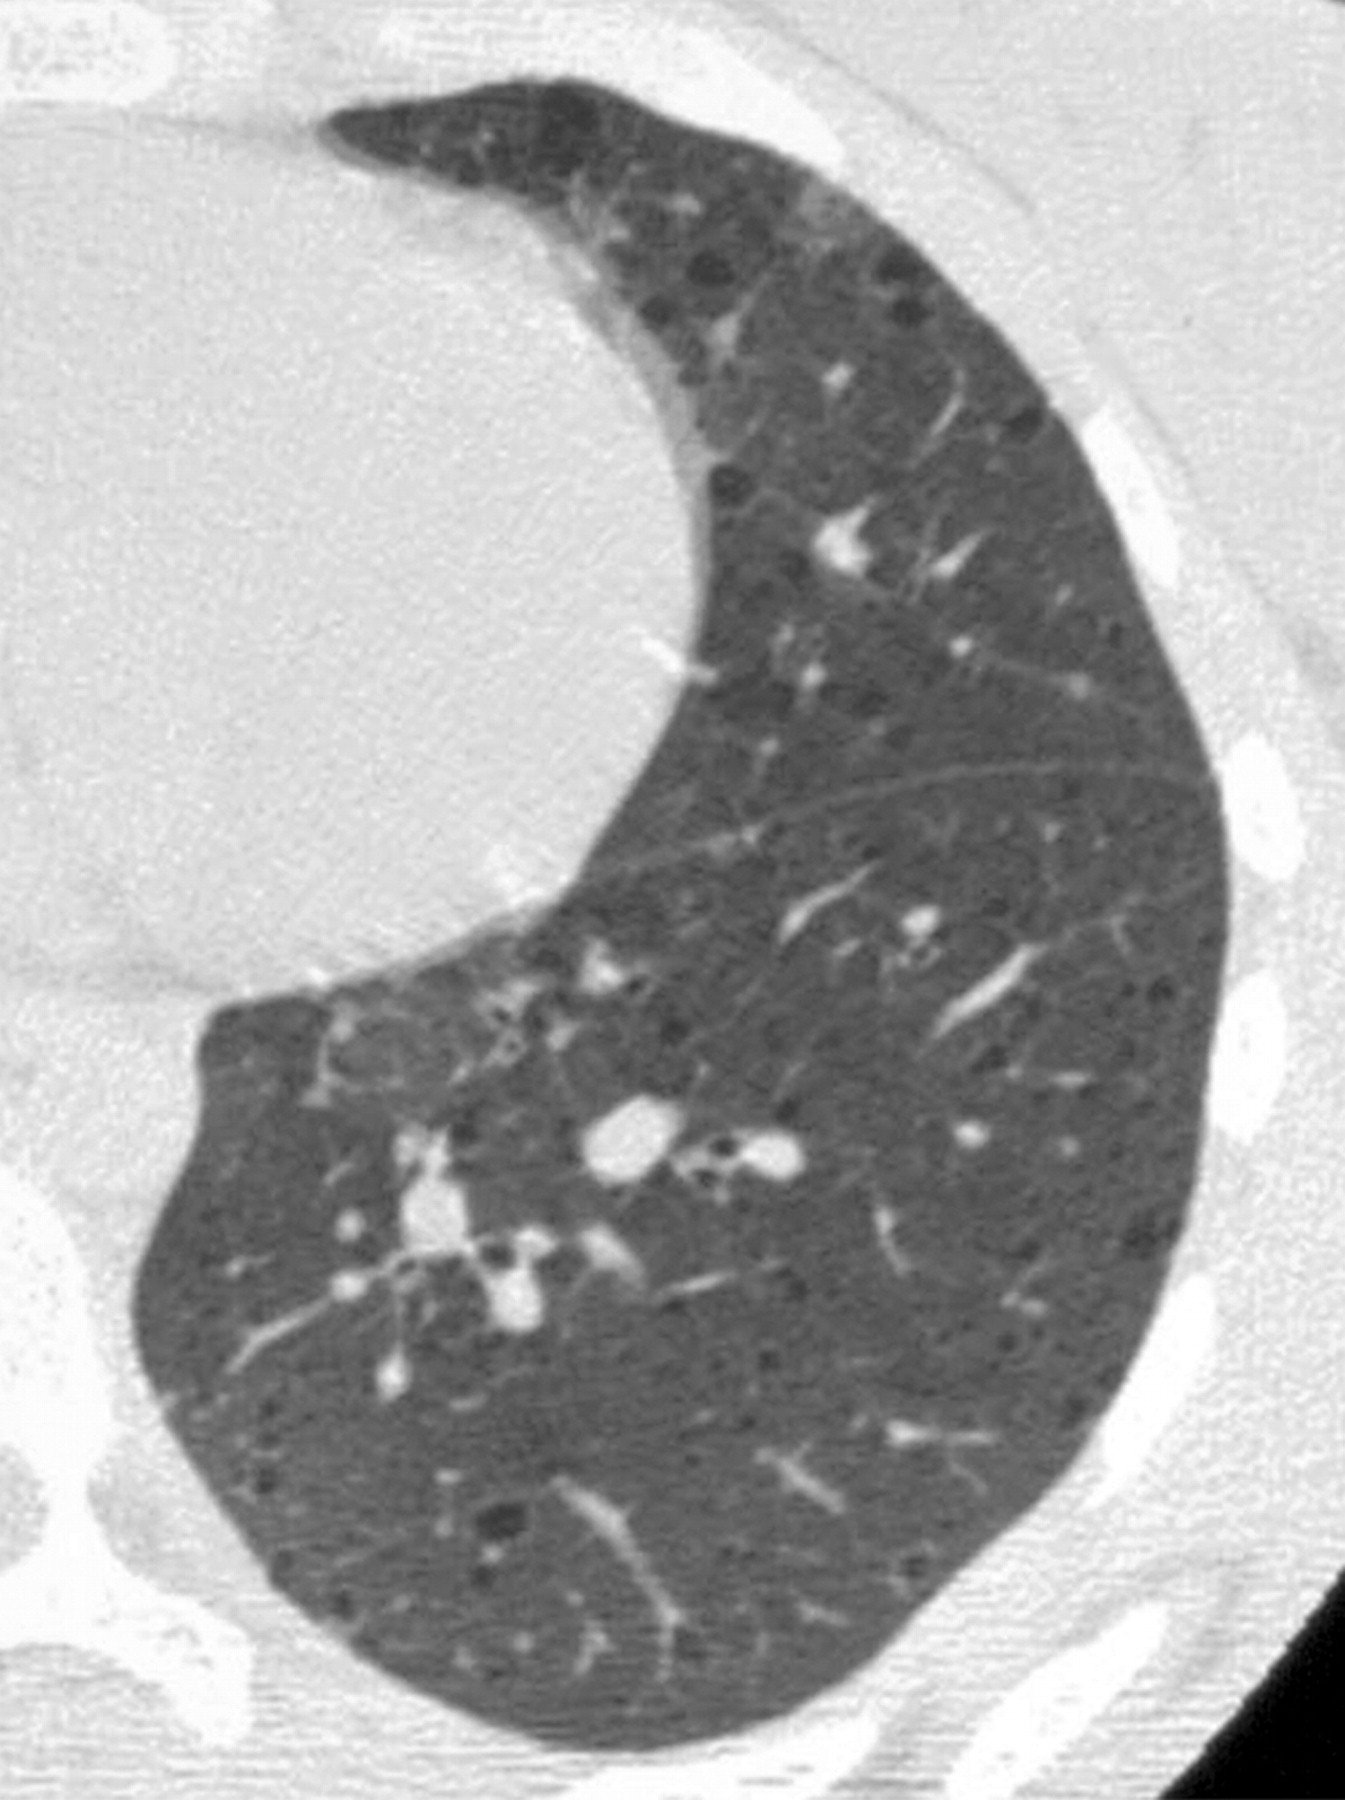

лимфангиолейомиоматоз

Типичный пример патологии при которой основным патерном являются кисты - :

Из архива AFIP. Лимфангиолейомиоматоз.

Лимфангиолейомиоматоз.